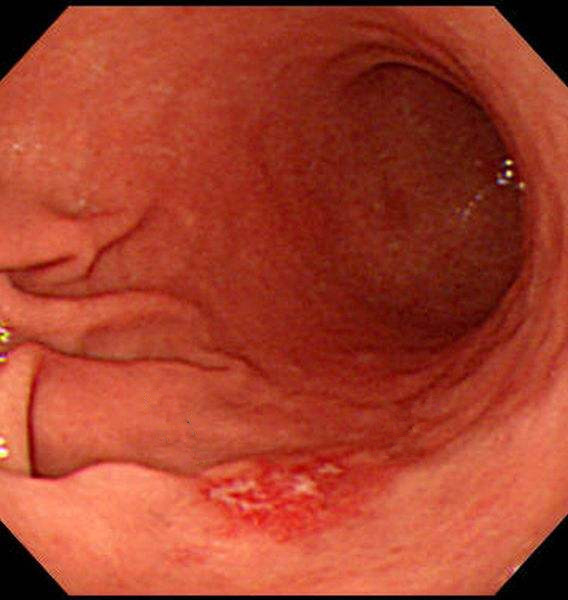

萎縮出血性慢性胃炎